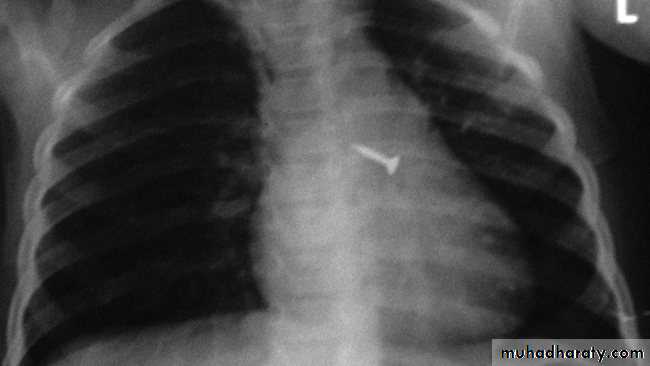

Foreign Body Inhalation

A common problem

Most common site for foreign body inhalation is?Clinical presentation:

• Asymptomatic only discovered by a witness• Stridor with dyspnea if stuck in the trachea or larynx

• wheezing with a persistent cough when in the bronchus

• repeated or persistent pneumonia with suppuration (late presentation).

Investigations:

Chest X-ray:

DDx: FB in the esophagus